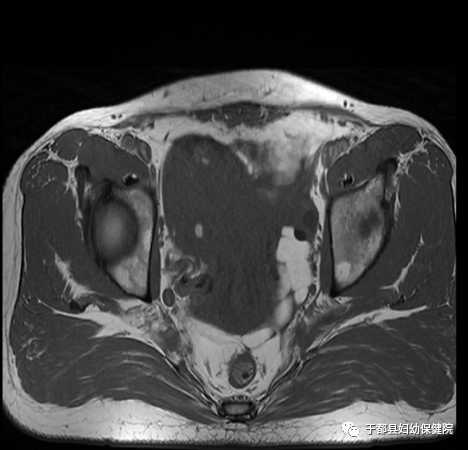

妇科检查:

磁共振(MR)成像无电离辐射、组织分辨率高、能多平面多参数成像,在显示女性盆腔解剖及疾病方面较超声和CT更具准确性和特异性。

子宫肌瘤:

不仅能显示肌瘤的大小、数目,且能清晰显示肌瘤在子宫的位置、与子宫肌层及与邻近器官和组织的关系。

子宫腺肌症:

结合带增厚是腺肌症特征性表现之一,可以准确区分子宫内膜、结合带和外肌层,对病变的显示具有明显优于其他检查。